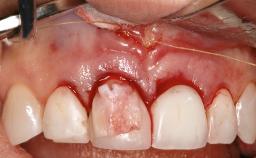

Treatment of Peri-Implant Mucositis at a Zirconia Implant

Frank Schwarz, Ausra Ramanauskaite

Recent clinical studies, most with short-to-medium term observation periods, have reported on the favorable clinical performance of zirconia implants in terms of survival rates, clinical, and radiographic outcomes (Roehling and coworkers 2016; Roehling and coworkers 2017; Rodriguez and coworkers 2018; Lorenz and coworkers 2019). Nonetheless, a rather high incidence of peri-implant disease at zirconia implants (39% of implants) was noted throughout a two-year period, highlighting the need for treatment protocols of peri-implant diseases at zirconia implants (Becker and coworkers 2017).